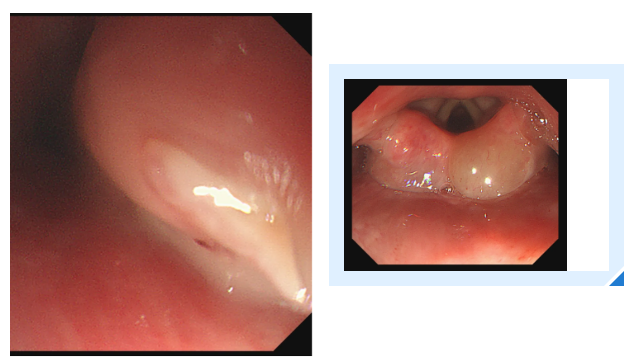

消化内镜室迅速启动取刺准备,当胃镜缓缓抵达食管入口时,清晰可见一根长约3cm的鱼刺,正斜斜嵌顿在食管入口的右侧壁,鱼刺尖端已刺入黏膜下层,周围黏膜因刺激出现明显充血水肿。更棘手的是,鱼刺恰好卡在食管入口的生理拐弯处,这个部位是食管与咽喉的衔接点,角度刁钻,内镜难以稳定固定位置。

操作医生首先尝试使用常规透明帽辅助取刺。透明帽顺利扩张开食管入口,将鱼刺完整暴露在视野中,但当异物钳从内镜操作通道伸出时,问题出现了:由于食管拐弯的角度限制,内镜操作通道与鱼刺的位置夹角过小,异物钳的活动空间被严重压缩。医生反复调整内镜角度和异物钳方向,要么视野被遮挡无法看清鱼刺,要么异物钳无法精准对准鱼刺主体,尝试了数次后,始终无法牢固夹持鱼刺,首次取刺宣告失败。